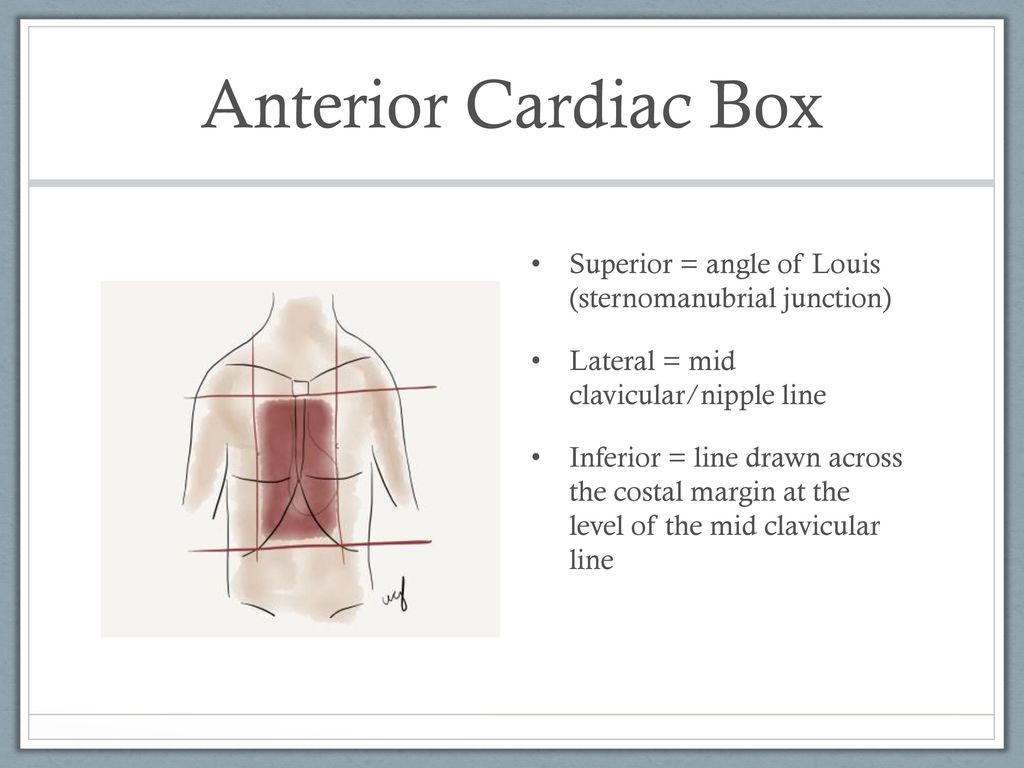

Trauma Anatomic Regions Ppt Download